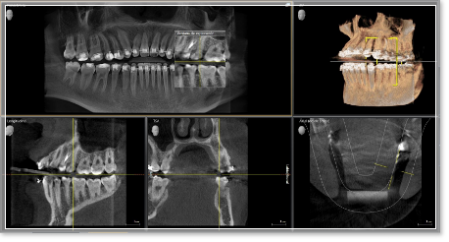

¿Cómo se inicia y diagnostica el tratamiento de ortodoncia?

El primer paso es realizar un estudio detallado mediante la realización de radiografías, fotografías o modelos de estudio para determinar cuál es la mejor opción de ortodoncia que debe seguir el paciente. Una vez seleccionado el tratamiento de ortodoncia se establece una planificación que podrá variar en función de la implicación del paciente en el cuidado y desarrollo del tratamiento.